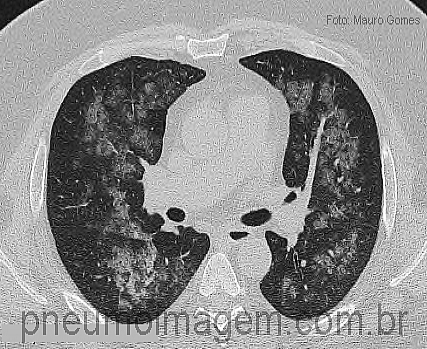

CASO CLÍNICO #16Homem, 60 anos de idade, compareceu ao Serviço de Emergência com tosse e dispneia há um dia com hemoptise. Referiu episódio de refluxo com sufocamento noturno. Avalie este corte tomográfico realizado à admissão e formule sua hipótese diagnóstica. Deixe seus comentários abaixo.

Man, 60 years old, went to the emergency room with cough and dyspnea for one day with hemoptysis. He referred reflux episode with nightly suffocation. Evaluate this CT slice performed at admission and formulate your diagnostic hypothesis. Leave your comment below.